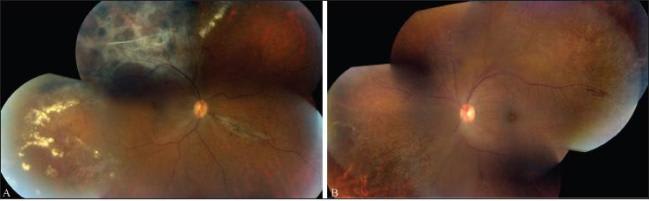

The patient was restarted on induction intravenous ganciclovir and HAART but again left AMA after six days of treatment. She returned in February 2010 complaining of worsening vision in both eyes. Visual acuity at that time was 20/60 in the right eye and 20/20 in the left eye, with the posterior-segment examination (Figure 3) demonstrating FBA and fulminant CMV retinitis in both eyes. The patient was again admitted and restarted on HAART therapy and intravenous ganciclovir for 14 days. She also received six intravitreal injections of ganciclovir (2,000 μg) and foscarnet (1,200 μg) in each eye. After induction, the patient was transitioned to oral valganciclovir (900 mg po daily) and discharged on HAART.

Figure 3. Fulminant CMV retinal necrosis and frosted branch angiitis in both eyes (A and B).